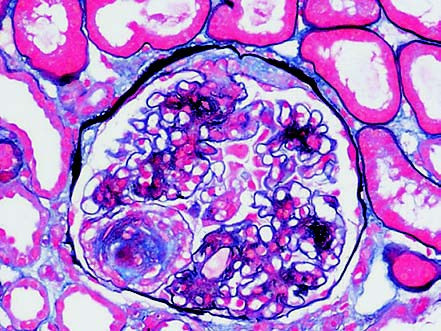

In light microscopy, glomerular hypertrophy and increased mesangial matrix expansion are observed. As the disease progresses, diffuse thickening of the glomerular basement membrane and mesangial proliferation occur, leading to the formation of characteristic Kimmelstiel-Wilson (K-W) nodules. These nodules are focal, lobulated, and peripheral mesangial lesions with a round to oval shape, consisting of acellular hyaline-like matrix, which is a relatively specific pathological feature of DKD and is referred to as nodular glomerulosclerosis. Tubular pathological changes include vacuolar degeneration of tubular epithelial cells, thickening of the tubular basement membrane, reduction of brush borders, and tubular atrophy. Interstitial and vascular changes include renal interstitial fibrosis, inflammatory cell infiltration, and arteriolar hyalinosis. Immunofluorescence reveals linear deposits of IgG and albumin along the glomerular and tubular basement membranes. Electron microscopy shows increased mesangial matrix, homogeneous thickening of the basement membrane, and early segmental podocyte foot process fusion, which becomes diffuse as the disease progresses.

Figure 1 Diabetic kidney disease with Kimmelstiel-Wilson nodules (PASM ×200)